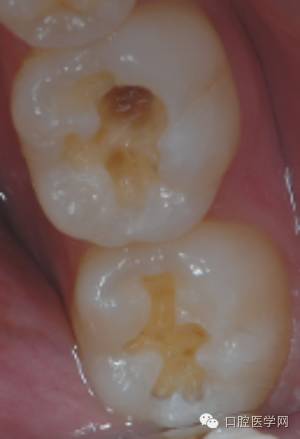

临床检查:36 37牙合面发育沟内探及龋损,探诊(—),叩(-),冷热诊无不适

诊断:36 37中龋

初始片

1、 评估牙体情况,患牙牙合面形态完整,可直接制作印章,若形成了破坏,可适当做一些形态补偿。

2、牙体颜色较为正常,简单比色后选用3M  Z350 body A3.5色,直接充填。